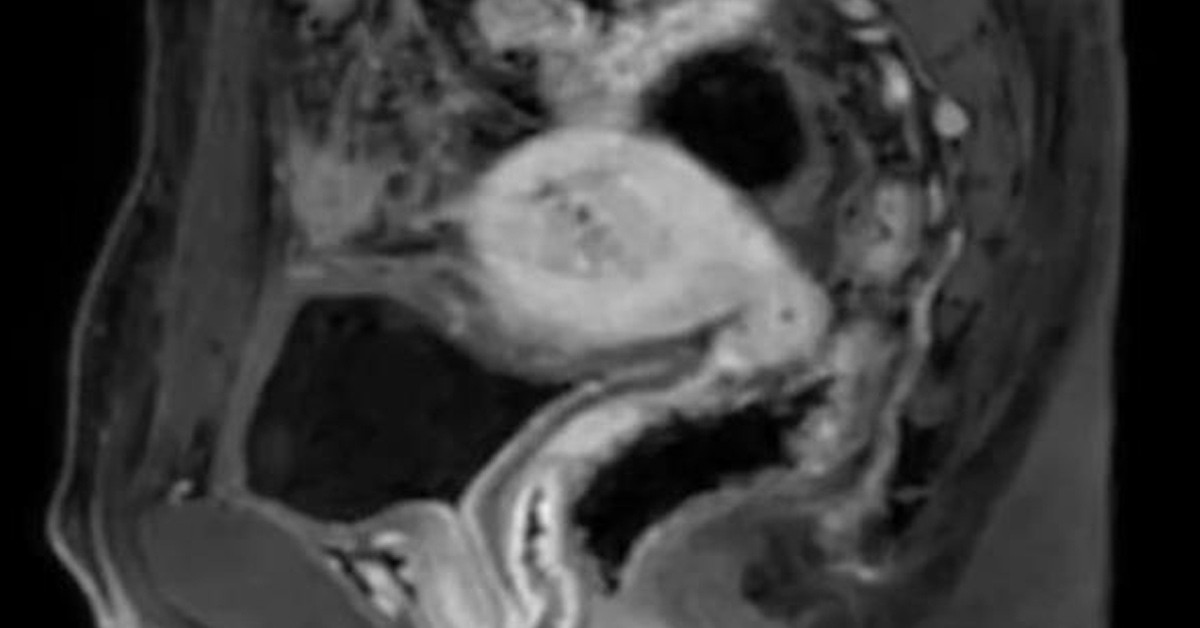

Doktorlar yaptıkları incelemede Chen Li’nin erkek organı dışında kadınlarda olduğu gibi bir rahmi ve yumurtalıkları olduğu belirlendi.

Otaya çıkan bu durum karşısında doktorlar şaşkınlıklarını gizleyemedi. İlk kez böyle bir durumla karşılaştıklarını belirttiler.

Daha sonra olan biten her şeyi Chen Li’ye anlattılar. 33 yaşındaki genç adamın 20 yıl boyunca adet gördüğü bu sebeple kanama gördüğü söylendi.